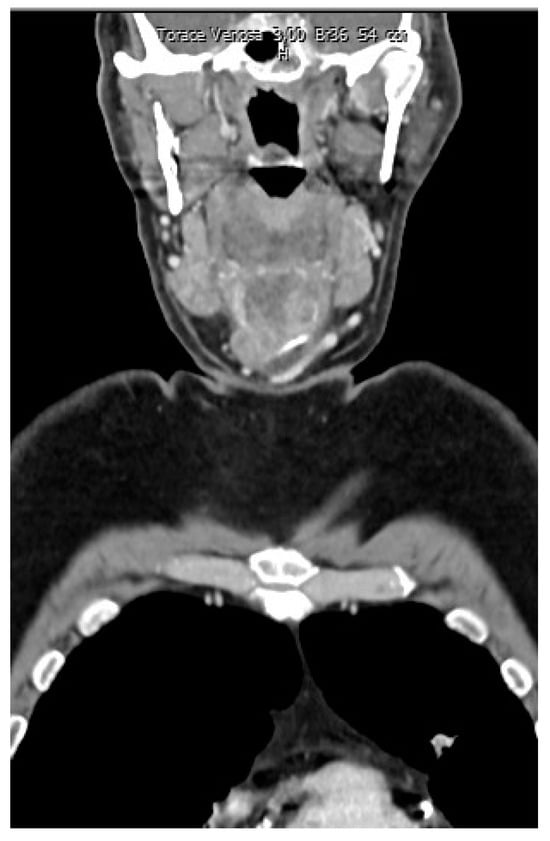

During the postoperative period, the patient received chemotherapy treatment. In that period, he also had a bone scintigraphy and an 18-F-FDG PET/CT. (Figure 7).

Figure 1. Contrast-enhanced computed tomography (CT) showed a rounded osteolytic mass of 4.5 × 3.6 cm in size in the central part of the hyoid bone: coronal view.

Figure 7. Postoperative 18-F-FDG PET/CT.